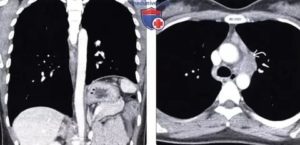

На сегодняшний день главный диагностический метод при выявлении липом – рентгенологическое обследование. Однако снимки, полученные с помощью рентген-сканирования, не всегда достаточно информативны для дифференциального диагноза. Поэтому в виде дополнительного обследования пациенту назначается компьютерная томография.

КТ. Грыжа диафрагмы – состояние, требующее дифференциальной диагностики с релаксацией купола диафрагмы

Поддиафрагмальный абсцесс, КТ брюшной полости с контрастированием. В правом надпеченочном пространстве под диафрагмой определяется скопление жидкости с горизонтальными «уровнями», а также множественные включения газа

При компьютерной томографии грудной клетки в заднем реберно-диафрагмальном синусе с левой стороны выявлено прилежащее к диафрагме образование, имеющее плотностью жира (около – 100 единиц по шкале Хаунсфилда). Подозрение на липому